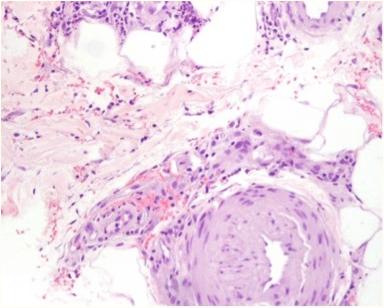

出院3周后,患者随诊诉*丸睾**疼痛15天,体重减轻(5KG)。体格检查发现腿部多发紫癜性病变伴溃疡、脓疱及溃烂(图1和2),手臂也发现瘀斑。皮肤活检显示角膜层脱落,角质形成细胞坏死和丰富的多形核细胞(图3),深部真皮及皮下动脉的多形核浸润伴血管炎的局灶性体征(图4),与结节性多动脉炎一致。患者接受泼尼松治疗,从60 mg开始,然后逐渐减少剂量,直到皮肤病变完全缓解。

图4HE染色显示动脉多形核浸润和血管炎的局灶性征象